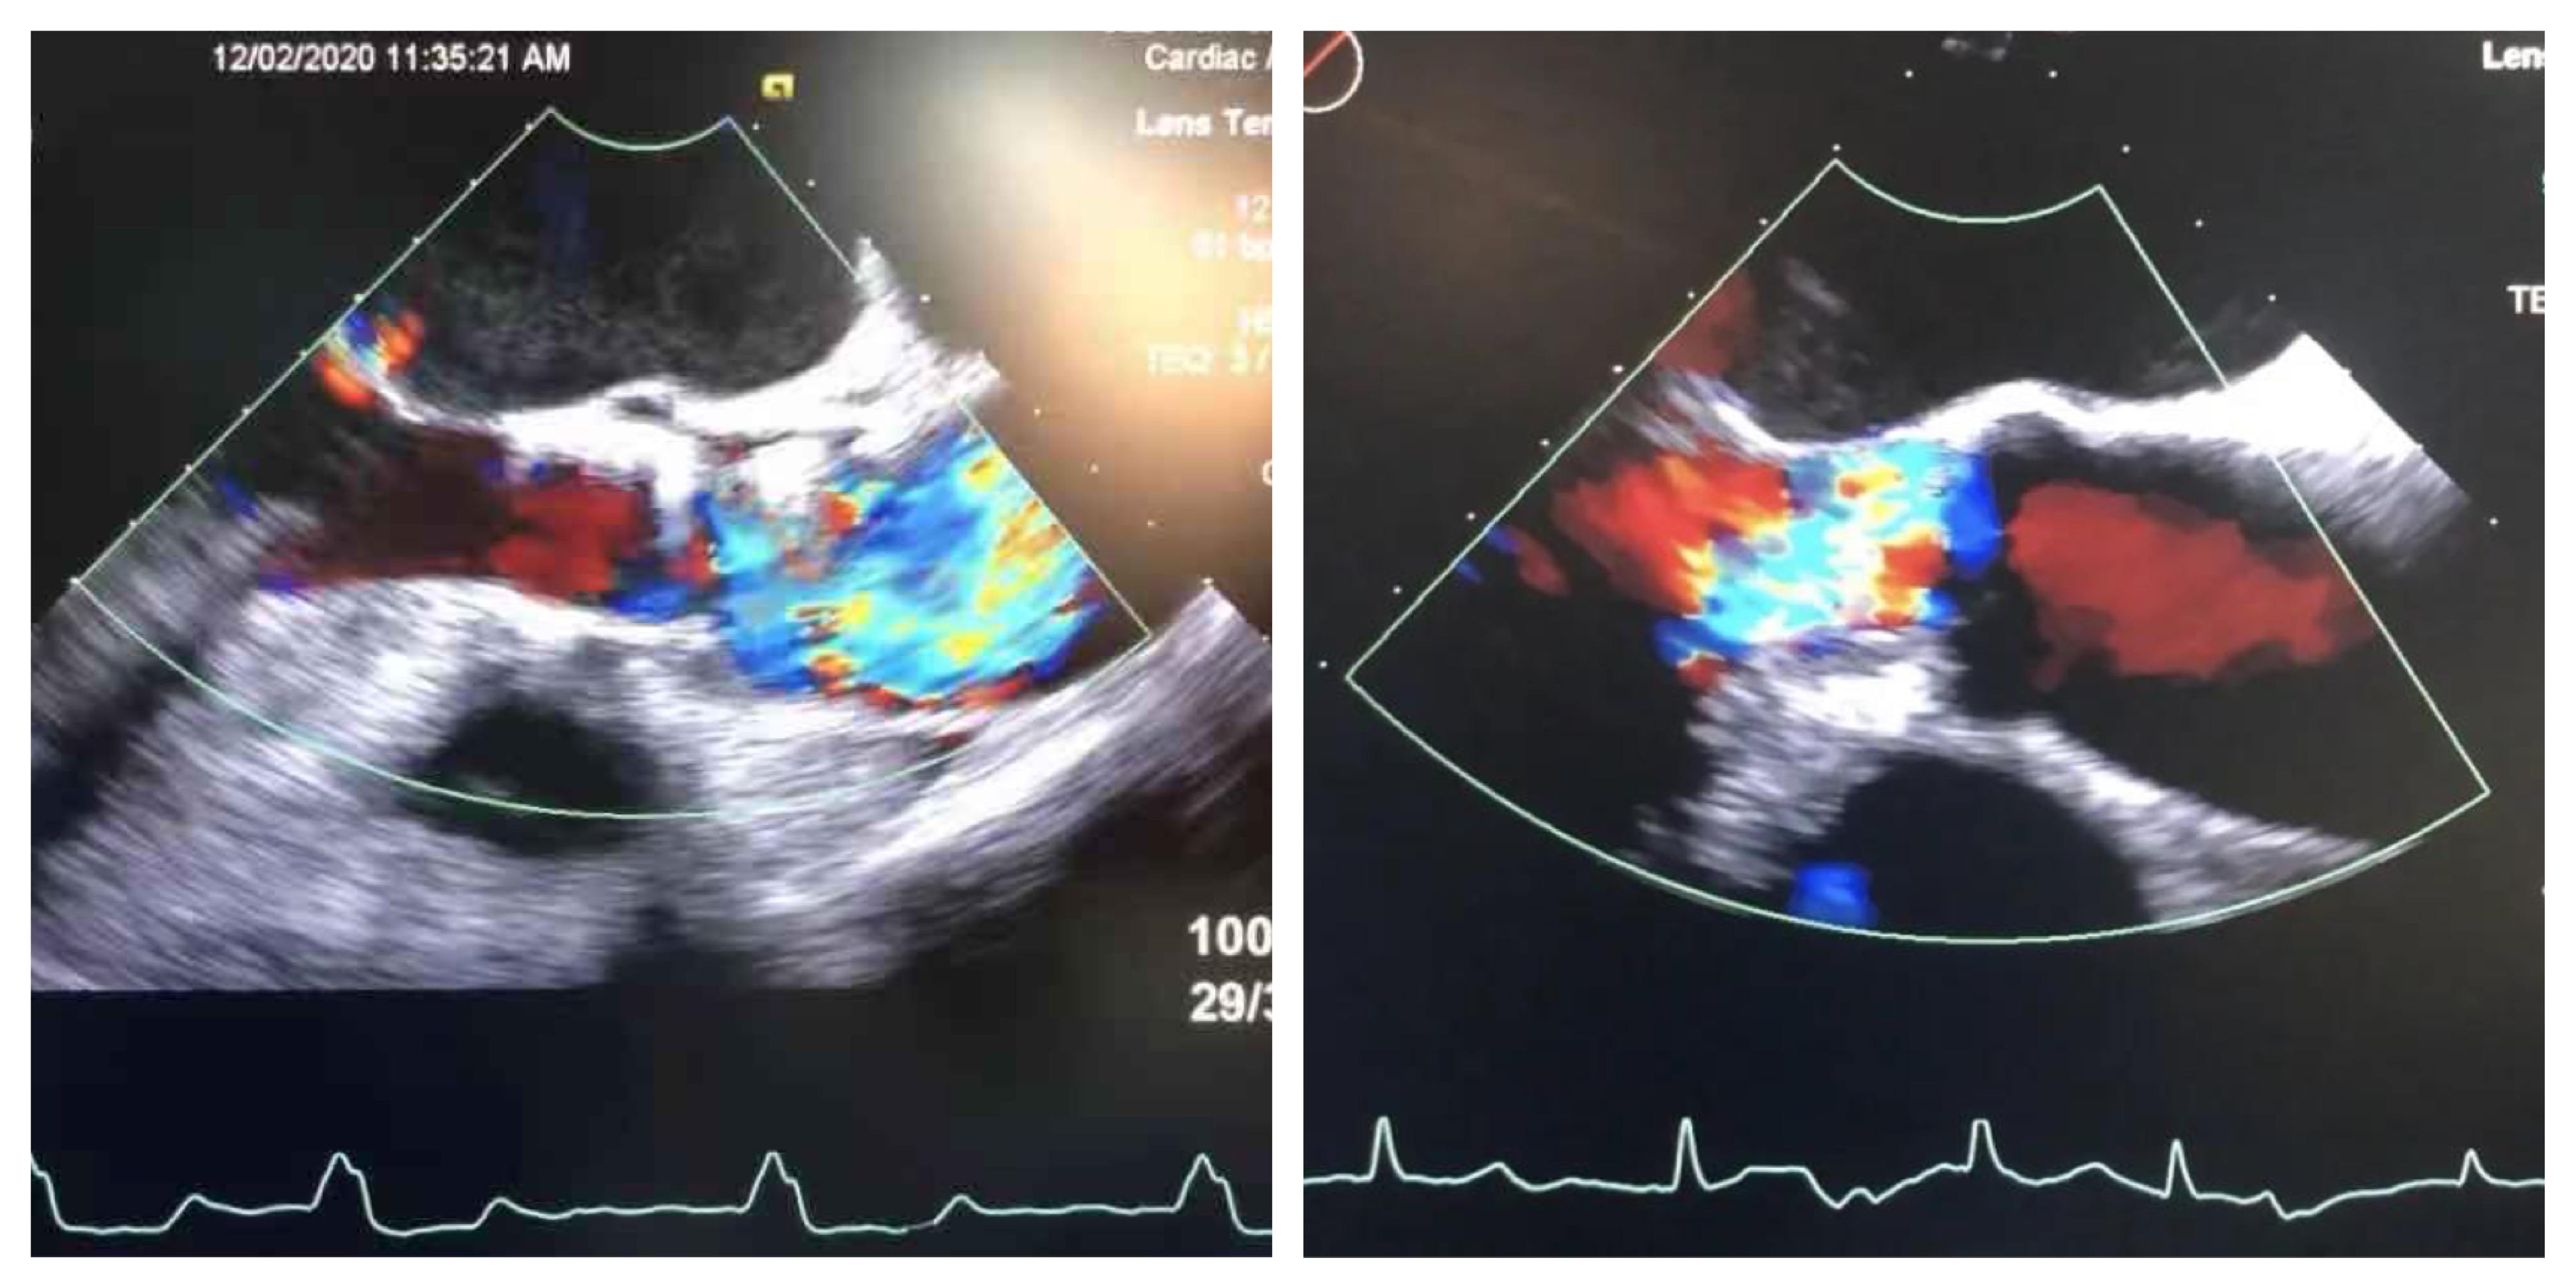

术前心超 术后心超